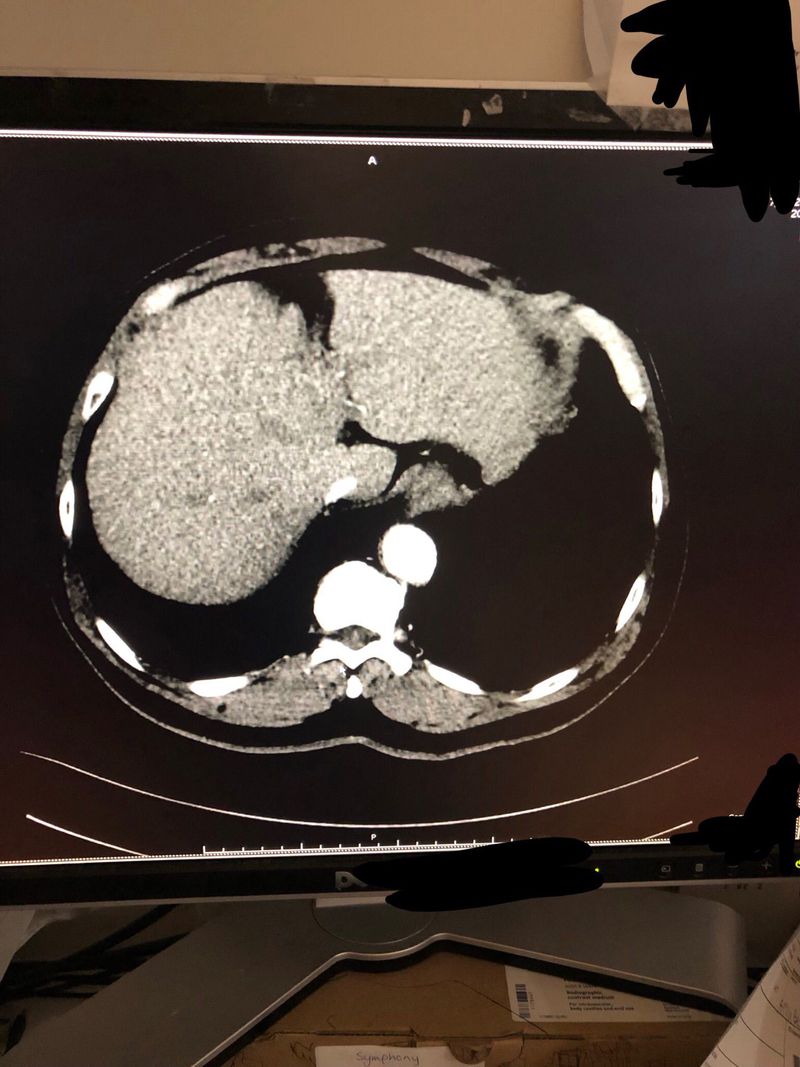

15kg weight loss... can you spot the cause?

Liver

Oncology

Pancreas